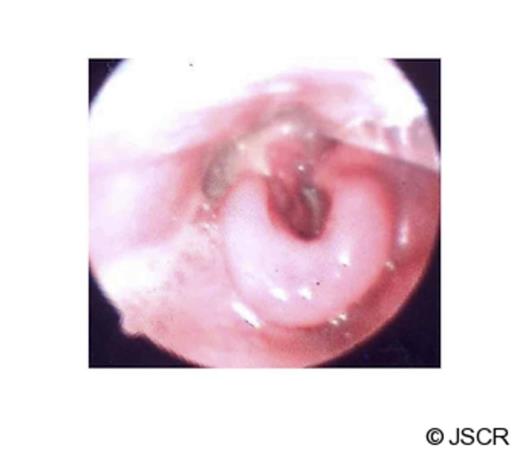

After the operation, the diagnosis was revised to isolated necrotizing fasciitis of the larynx. The necrosis of the larynx was closely monitored. A combination of empirical antibiotic therapy was prescribed under guidance of microbiologist (Table 1). The antibiotic regimen made significant improvements in the laryngeal oedema (Fig 2), resolution of necrosis and inflammation of the laryngopharynx.